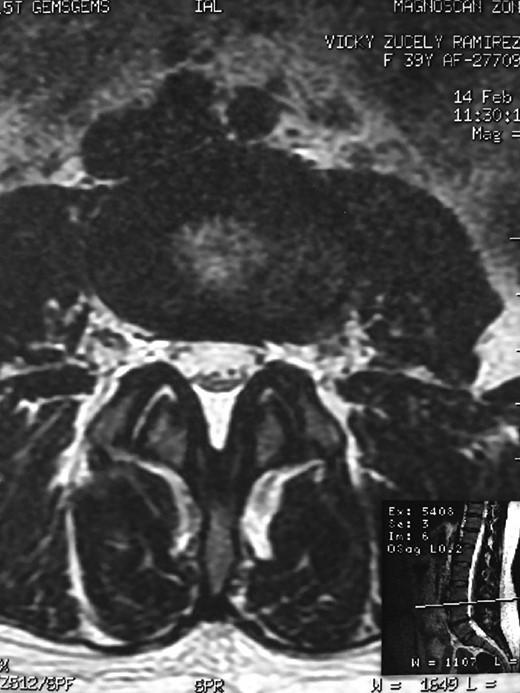

A 42-year-old female presented to the clinic with a history of chronic low back pain. She reported no relevant medical history. She had already been treated in the last 4 years by general practitioners with analgesics and home based physiotherapy with no satisfactory results. She had two previous admissions to the emergency department where morphine was prescribed to control the pain on her lower back. She was under ambulatory treatment with diclofenac, and tizanidine with partial relief of symptoms. Her main complaint was pain on the lower lumbar back with no radiation to the lower extremities. In her physical evaluation she presented limitation to full rotation and bending of the lumbar spine due to pain. Lasegue sign was negative, sensitivity, reflexes, sagittal balance, distal muscular strength and pulses were normal. Radiographs showed an overdeveloped left transverse process of the fifth lumbar vertebra which contacts with the sacrum at the left sacral wing with signs of degeneration at the same site (Fig. 1). Magnetic resonance imaging (MRI) studies were obtained (Figs 2–5). The patient was taken to the operating room where infiltration with 1 mL of lidocaine and 40 mg of Triamcinolone was performed in the pseudoarticulation between the left transverse process and the sacrum under fluoroscopic guidance. She reported a complete relief of pain after the procedure. At three months follow-up she was managed with strengthening and stabilizing exercises for the lumbar spine and postural education was initiated. She remains asymptomatic at her 12 months follow up.

Degenerative changes at the facets and disc in the adjacent segment.

The partial fusion at the lower part of the lumbosacral transition produces important alterations in normal biomechanics at the levels immediately above and below the LSTV. Changes such as hypermobility and abnormal torque moments are present at the level above the LSTV, predisposing it to early degeneration (early disc pathology and facet joint degenerative disease). Restricted movement below the LSTV produces a protective effect against degeneration of disc and facets and is related to changes (facets are smaller and coronally oriented) in the dimensions of the lower level facet joints [7]. These alterations can be verified in the adjacent levels of the LSTV in our patient.